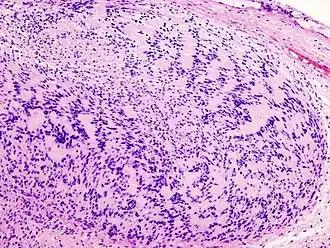

Illustrations

Neurinome subcutané_Antoni_B.jpg)

_Antoni_B.jpg)

_S-100_immunostain.jpg)